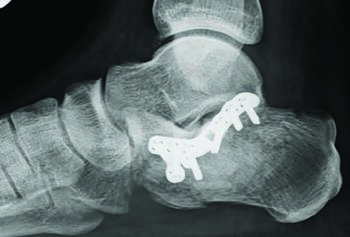

A Closer Look At Calcaneus Fractures

Injuries resulting in calcaneal fractures are usually high velocity in nature and are associated with proximal polytrauma. The fractures in the calcaneus seen from these types of injuries are oftentimes multiple and result in lateral wall blowout. Due to the forces seen in these injuries further soft tissue injury from surgery is a concern. The main goals in reducing calcaneal fractures are to maintain the height and length of the calcaneus, and to preserve as much of the STJ articulation as possible in proper alignment. This can be facilitated through Schantz or Steinmann pins into the calcaneal tubercle placed percutaneously to restore the height and length through manual traction. The basic minimal incision approach to calcaneal fractures entails a sinus tarsi approach instead of a large lateral extensile incision. Further reduction of the anterior process, and posterior facet of the STJ articulation can be achieved through percutaneous K-wire fixation from the lateral wall and incorporating the sustentaculum tali medially. The calcaneal plate can be introduced in much the same manner as the MIPO technique seen in pilon fractures. The main incision is usually placed lateral to the Achilles tendon insertion with the length that allows full introduction of the calcaneal plate. Posterior screw fixation can be introduced through this larger incision. Two minimal incisions can often times be utilized to place the remaining anterior and middle cluster of screws. The final reduction and fixation are checked under fluoroscopy before closure. Long-term data of percutaneous calcaneal fracture fixation of Sanders II and III fractures at 16 years shows ‘essentially normal’ function.12 Arthroscopic debridement is oft employed here to facilitate reduction and confirmation of joint surface restoration. The authors typically advocate for a sinus tarsi approach with plate/screw fixation with a final arthroscopic confirmation of fracture reduction at closure.